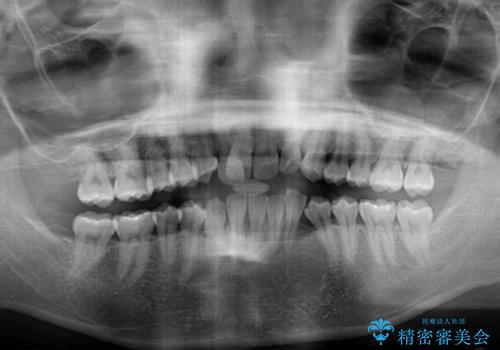

- 右上の八重歯と、左下八重歯を抜いてしまったことを気にして来院された患者様です。

下顎は既に犬歯を1本抜歯しているため、上顎右側第一小臼歯を抜歯し、ワイヤー装置にて歯列を整えることとしました。

変則的な抜歯となるため、正中と人中がずれる可能性がありましたが、仕上がりは上下正中を揃えることができました。